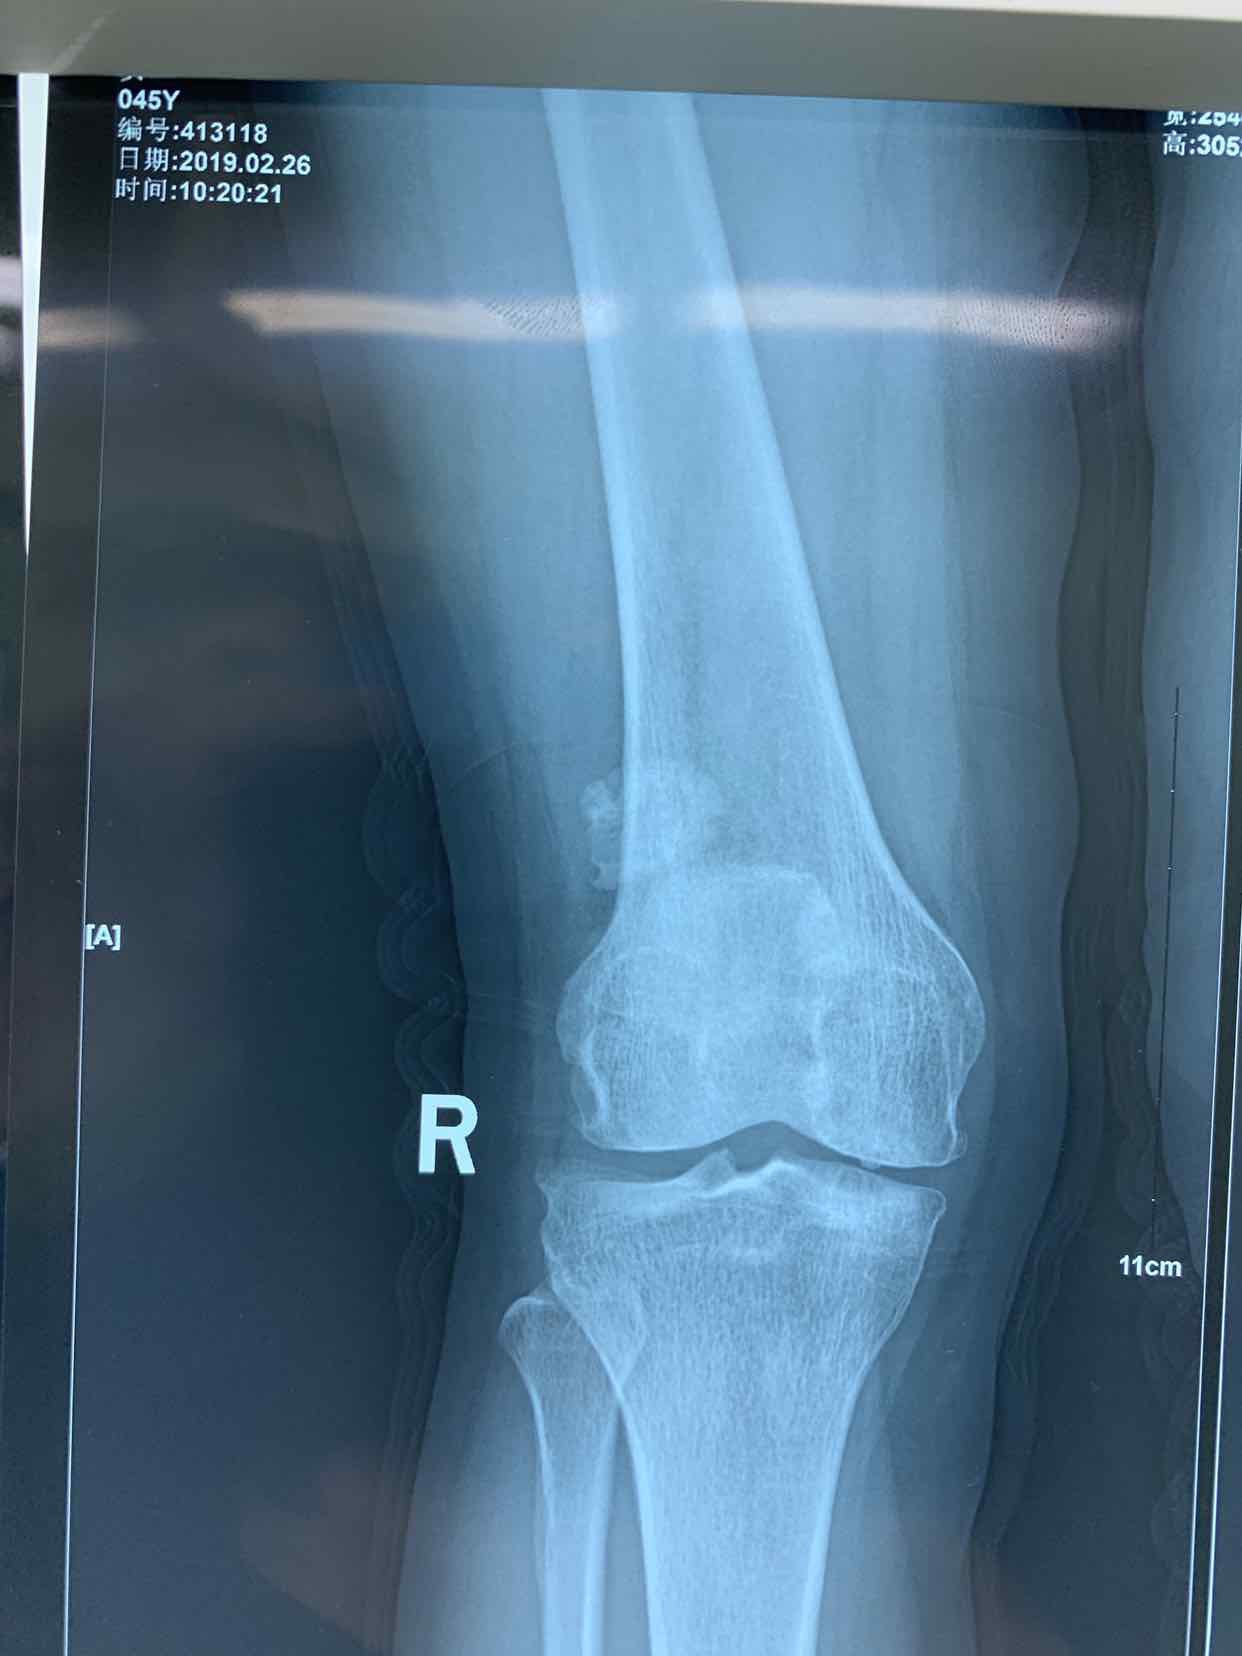

患者因双侧膝关节骨性肿物发现二十余年。收入院。患者无二十余年前无明显诱因发现双侧膝关节内有骨性肿物。异常活动。偶尔在屈曲活动时出现局部嵌夹于关节内。疼痛。不能活动。并弹响。近半年内肿物增大。疼痛发作频繁。遂来诊。门诊拍片提示见双侧膝关节内骨性游离体,位于关节内。门诊以双侧膝关节游离体收入院。

查体见患者双侧膝关节局部肿胀。压痛。可于局部触及骨性肿物在关节内游走。屈伸活动时偶有嵌顿。行走活动受限。拍片提示双侧膝关节骨性游离体。